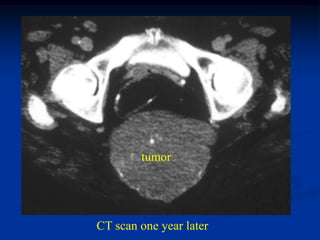

Case #1099

53 year female with chordoma sacrum

Bone scan

Oblique bone scan

tumor

CT scan one year later

Sagittal T-2 MRI

Axial T-2 MRI